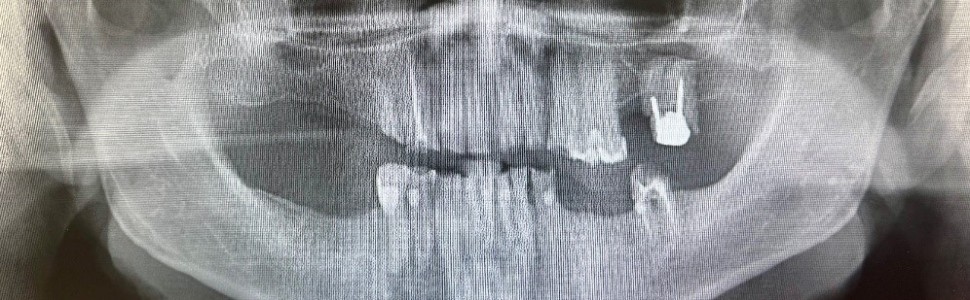

W pracy opisano algorytm postępowania w trzech przypadkach klinicznych zaburzeń układu stomatognatycznego, których następstwem było patologiczne starcie zębów. Zwrócono szczególną uwagę na kompleksowe podejście do leczenia oraz na konieczność leczenia kilkuetapowego. W pierwszym etapie terapii u wszystkich pacjentów wykorzystano technikę iniekcji płynnego kompozytu, a w drugim etapie wykonano docelową odbudowę w zależności od indywidualnych warunków klinicznych.

This paper describes the procedure in three cases of stomatognathic system disorders resulting in pathological tooth wear. Particular attention was paid to the holistic approach to treatment and the necessity of more stage treatment. In the first stage of treatment, the technique of liquid composite injection was used in all patients, and in the second stage, the final restoration was performed depending on the individual clinical conditions.